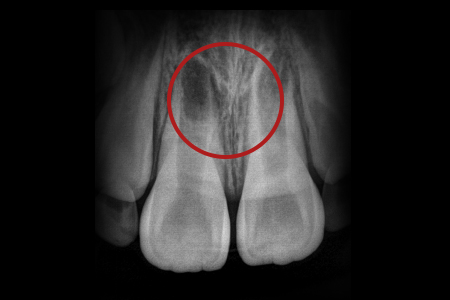

과잉치란 정상적인 치아 수 외에 추가적인 치아가 더 존재하는 경우를 말합니다.

특히 윗 앞니 가운데에 위치한 정중 과잉치는 앞니 사이를 벌어지게 하는 부정교합의 원인이 될 수 있기 때문에 제거해야 합니다.